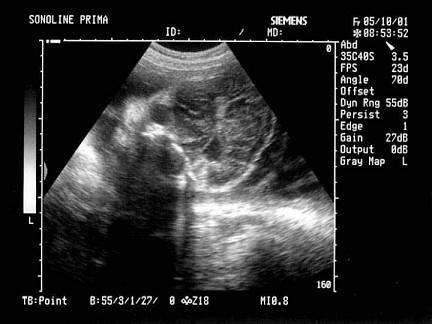

问题 女性,29岁,停经28周,产前超声检查如图,最可能的诊断为?(?)

选项 A.胎儿畸形,脑积水 B.胎儿畸形,腹壁裂 C.胎儿畸形,室间隔缺损 D.胎儿畸形,无脑儿 E.胎儿畸形,露脑畸形

答案 D